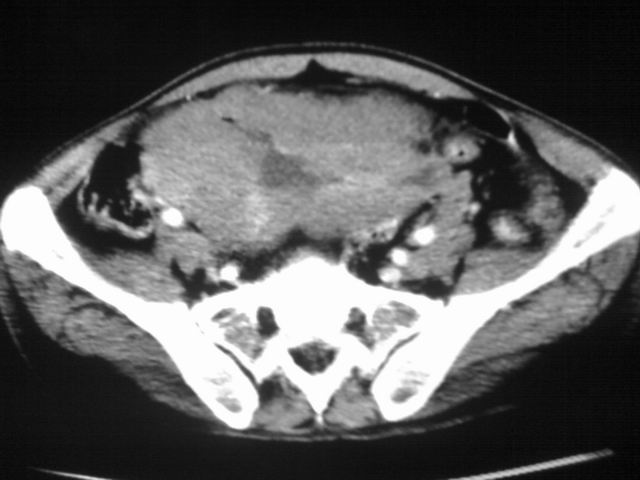

患者m 56岁,盆腔及下腹部胀痛半年,加重1月余,消瘦\中重度贫血.(附:平扫时直肠的高信号为,残留的钡剂).补一下病史:胃镜及纤维结肠镜均无明显异常.

首先是病灶的定位,平扫看很象肠管肿瘤但既然纤维结肠镜正常就可以除外结肠病变,增强成不均匀强化,位于右下腹部应该首先考虑回肠末段占位性病变,1淋巴瘤,2间质瘤,3腹膜后神经原肿瘤待除外,

膀胱后方及直肠前方见巨大混杂密度影,与前列腺相连且向膀胱内突入,精囊腺显示不清;考虑前列腺癌侵犯精囊、膀胱。

膀胱及直肠间有不规侧的软组织密度影,内密度不均匀。其内有坏死囊变,前列腺及精囊腺,膀胱后壁受浸。结合病史考虑腹膜后肉瘤可能性大。